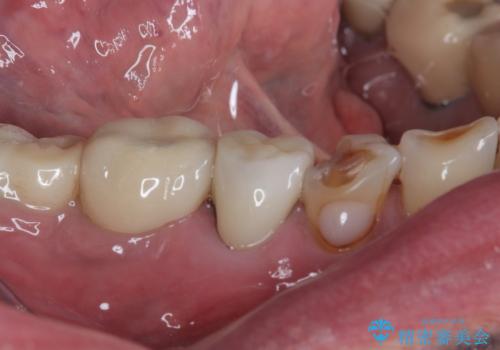

- 食事中に歯が欠けてしまったとのことで来院された患者様です。

以前詰めた材料が外れたか、歯が欠けたのかは分かりませんが、欠損している状態でした。

再度詰め物での処置を行うと引き続き欠けるリスクが高いため、高強度のフルジルコニアクラウンにて補綴治療を行うこととしました。

フルジルコニアクラウンは高強度であるため、クラウンの破損リスクは低減されましたが、失活歯(神経を取り除いた)では歯根破折リスクが高いとされており、抜歯の可能性が高まるため適用されません。